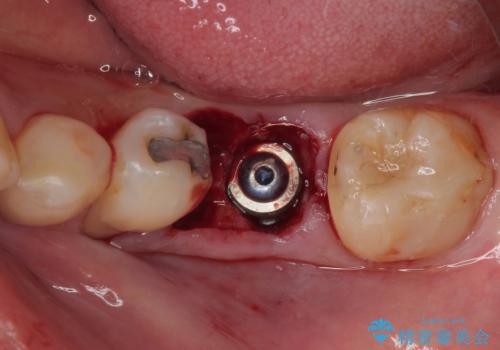

下顎大臼歯の抜歯即時埋入インプラント治療では、複数ある歯根のうち、後方の歯根部にインプラントを埋入することで一般的であり、今回破折して骨吸収が著しいのは前方の歯根であったため、事前に仮歯を用意した上で、抜歯即時埋入インプラントによる補綴治療を行うこととしました。

来院されるまではインプラント治療を躊躇されていましたが、抜歯即時埋入により、単回の外科処置で治療が終えられることのメリットを理解され、インプラントによる補綴治療を行いました。

スムーズに治療を終えることができました。